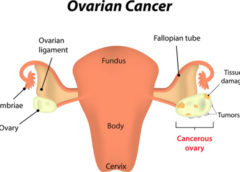

LeggiCisti ovariche semplici non necessitano di ulteriore monitoraggio

Le cisti ovariche semplici che vengono scoperte ecograficamente non sono associate ad alcun incremento del rischio di tumore ovarico e non devono essere seguite mediante ulteriori ecografie, ma se l’ecografia rivela una cisti complessa o una massa solida il rischio di tumore ovarico è…

LeggiTumore ovarico: metilazione BRCA1 predice responsività al rucaparib

Le cellule di carcinoma ovarico che presentano metilazione di tutte le copie di BRCA1 hanno maggiori probabilità di risposdere al PARP-inibitore noto come rucaparib. Lo suggerisce uno studio condotto su 17 pazienti da Clare Scott del The Walter and Eliza Hall Institute of Medical…